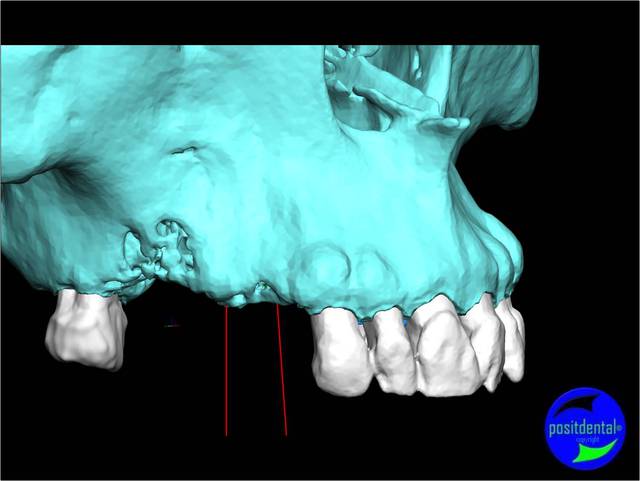

- la planification implantaire en 3D

Cas clinique n° 1

Guide chirurgical 001 rnxpkn - Eugenol

Guide chirurgical 002 vtt1yt - Eugenol